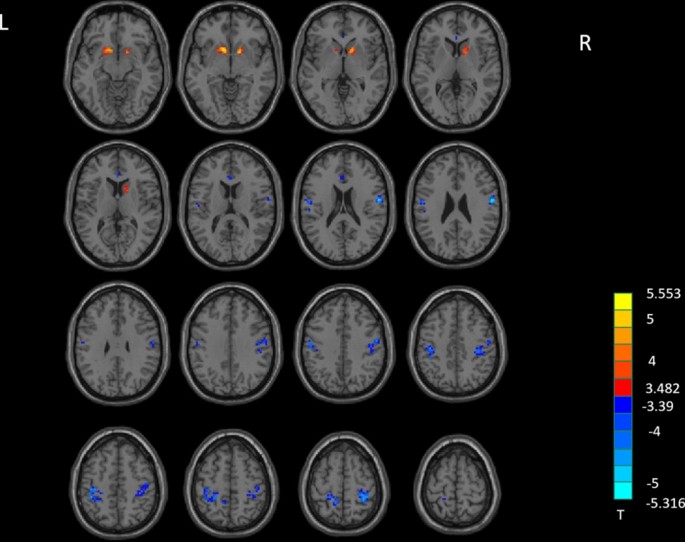

Compared to HCs, MADs showed significantly increased fALFF in the left caudate extending to left putamen, right pallidum extending to right putamen, and right caudate (Fig. 1, Table 2). MADs showed significantly decreased fALFF in left inferior frontal gyrus (IFG) compared to HCs.

fALFF analysis. Two-sample t-test results are presented, voxel-level p < 0.001, cluster level p < 0.05, two-tailed, voxel size > 9, corrected by GRF. The area in blue represents significantly decreased ALFF value; the area in yellow and red represents significantly increased fALFF value. Created with DPABI_V4.3_200401 (http://rfmri.org/dpabi).